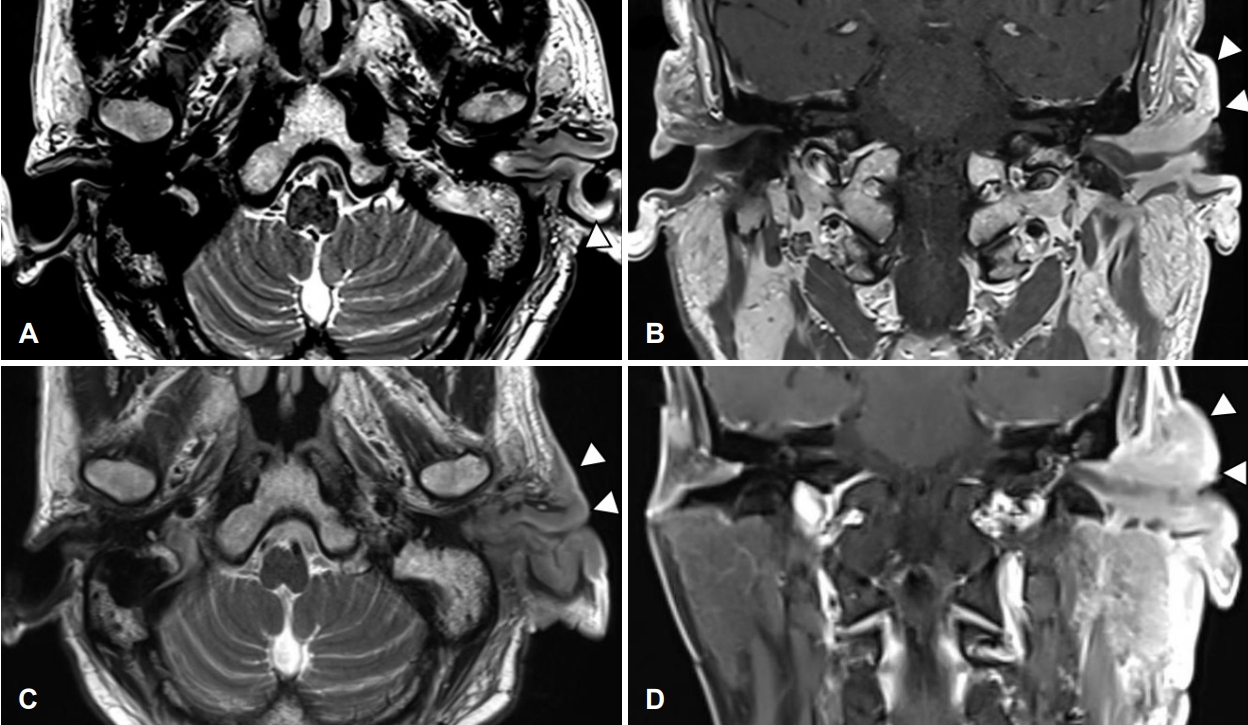

환자 본인의 의사로 타 병원으로 전원 하였고, 본원 최초 내원 두 달 후 타 병원에서 시행한 측두골 자기공명영상에서 좌측 외이도와 이개부 연조직의 부종, 이하선 및 주변 림프절 비대소견으로 염증성 병변과 함께 종양성 상태 의심 소견이 보고되었다(Fig. 4). 재내원 시 병변의 범위는 후이개까지 확장된 악화소견이 관찰되었다(Fig. 2E and F). 환자는 본원에서의 치료 지속을 원하여 양전자컴퓨터단층촬영을 시행하였으며, 좌측 외이도, 이개부 및 이하선을 포함한 불규칙한 과대사성 병변이 관찰되어 악성종양이 여전히 의심되었다(Fig. 5).

NotesAuthor Contribution Conceptualization: Tae Hoon Kong. Data curation: Dong Hwan Kwon. Funding acquisition: Tae Hoon Kong. Investigation: Minheon Kim. Project administration: Tae Hoon Kong. Supervision: Tae Hoon Kong. Visualization: Minheon Kim. Writing—original draft: Joo Hyung Lee. Writing—review & editing: Joo Hyung Lee, Tae Hoon Kong. Fig. 1.Initial ear findings and audiometry of the patient on first visit. A: Initial skin and soft tissue inflammation (post start of treatment day 21). B: Pure tone audiometry shows the air-bone gap (35 dB) of the left ear (red: right ear, blue: left ear). Fig. 2.Skin and soft tissue inflammation. Redness and swelling aggravated during antibiotic therapy and daily wound care. A: Post start of treatment day (PTD) 40. B: PTD 46. C: PTD 64. D: PTD 69. E: PTD 93. F: PTD 99. Fig. 3.CT of neck. 3.4×2.3×2.9 cm sized enhancing mass-like lesion at left external auditory canal and left ear auricle with enlarged lymph nodes at periparotid region. A: Coronal view. B: Axial view. C: Axial view of enlarged lymph node. Fig. 4.MRI of temporal bone. Subepithelial soft tissue thickening in the external auditory canal (cartilaginous portion) and auricle aggravated during antibiotic therapy and daily wound care. A: Post start of treatment day (PTD) 16, T2 weighted image (T2WI) axial. B: PTD 16, T1 weighted image (T1WI) coronal. C: PTD 96, T2WI axial. D: PTD 96, T1WI coronal. Fig. 5.PET-CT scan (torso). Left external auditory canal and left ear auricle, periauricular area, left parotid gland involving irregular hypermetabolic lesion was seen. Fig. 6.Histological findings. Polymorphous lymphoid cells infiltrate lacing cytologic atypia on PTD 112 compared to previous study. A: Post start of treatment day (PTD) 16, ear, Lt (hematoxylin and eosin [H&E], ×200). B: PTD 24, ear, Lt (H&E, ×200). C: PTD 58, parotid gland, Lt (H&E, ×200). D: PTD 112, ear, Lt (H&E, ×200). E: PTD 112, ear, Lt (CD3, ×100). F: PTD 112, ear, Lt (Epstein-Barr virus in situ hybridization, ×100 view). Fig. 7.Skin and soft issue inflammation has shown much improvement and epithelization of the wound was achieved after six months of treatment (post start of treatment day 174). Table 1.Differential diagnosis of chronic active Epstein-Barr virus of T-cell type REFERENCES1. Wauchope J, Dorris CB, Smith CP, Hanna B. Chronic active Epstein-Barr virus: A multidisciplinary approach. BMJ Case Rep 2020;13(12):e236287.